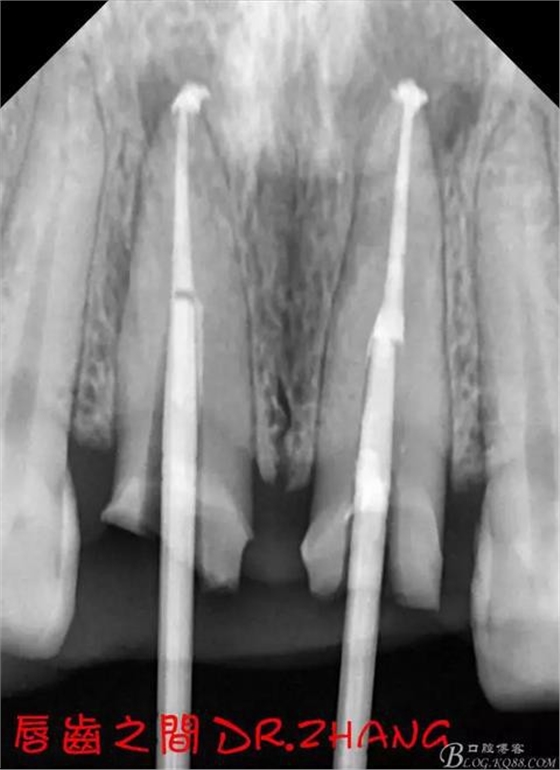

X片示11 21根管內(nèi)有高密度陰影 根尖低密度陰影

診斷:11 21慢性根尖炎

處理:21從修復(fù)體舌側(cè)打開通路 髓腔內(nèi)疑似纖維樁 高速和低速手機聯(lián)合去除樁核 在處理的過程中不斷拍片確認方向 去除樁核后拔髓針去除牙膠 只有一個標尖 膿液大量滲出 雙氧水和鹽水交替沖洗后 滲出減少 開放髓腔 隔日復(fù)診